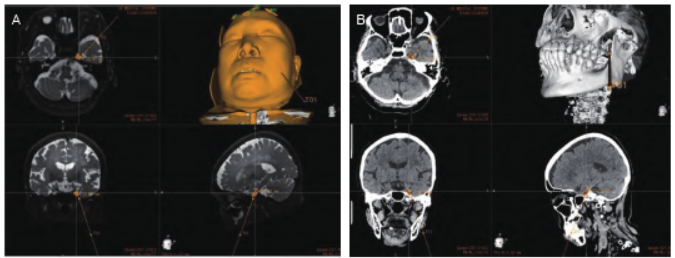

气管插管全身麻醉,仰卧位,头略后仰,塑形枕固定头部。采用睿米机器人导航定位,术前将病人CT 及MRI 等多模态影像资料导入进行融合,可以清晰呈现颅内三维立体结构,为手术规划提供准确信息,该病人以左侧三叉神经半月节为靶点,规划经左侧面部穿卵圆孔到达Meckel 腔的穿刺路径。

图1 术中机器人重建影像及穿刺路径设计(A)术中MR;(B) 术中CT